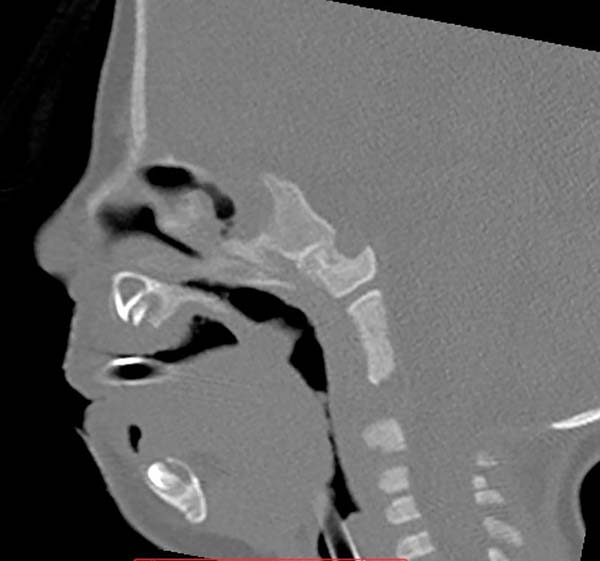

Os autores, intrigados com a discrepância entre grau de obstrução respiratória/dificuldade alimentar e grau de retrognatismo da mandíbula, voltaram sua atenção para uma alteração eventualmente encontrada no posicionamento do músculo genioglosso, observando seu encurtamento e firme aderência à sínfise mandibular, impedindo a protração lingual e podendo ser a causa de rotação lingual posterior e obstrução supraglótica6 (como mostrado na Figura 1, a posição lingual alterada, com consequente glossoptose).

As imagens evidenciam resultados da ortoglossopelveplastia na melhora da obstrução supra glótica (Figura. 12) e na evolução de paciente com Pierre Robin e dificuldade alimentar tratado apenas com ortoglossopelveplastia, evidenciando posterior crescimento mandibular pela correção das suas forças de crescimento (Figura 13).